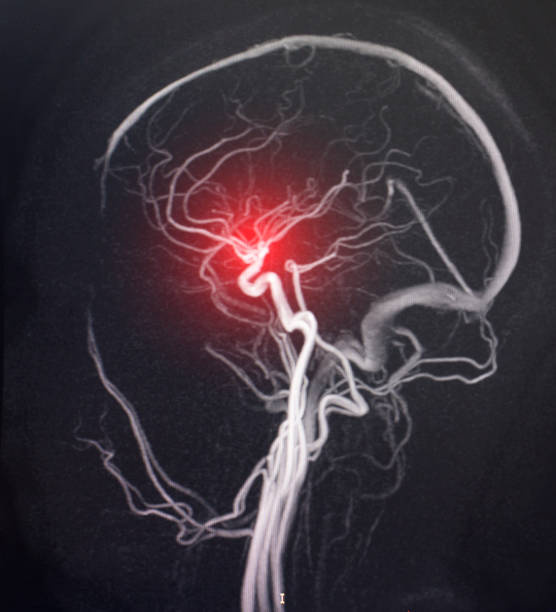

과천 PT | 뇌출혈 초기증상, 두통 절대 가볍게 넘기지 마세요

일상에서 흔히 겪는 증상 중 하나인 두통. 하지만 어떤 경우에는 생명을 위협하는 신경계 응급상황의 신호...